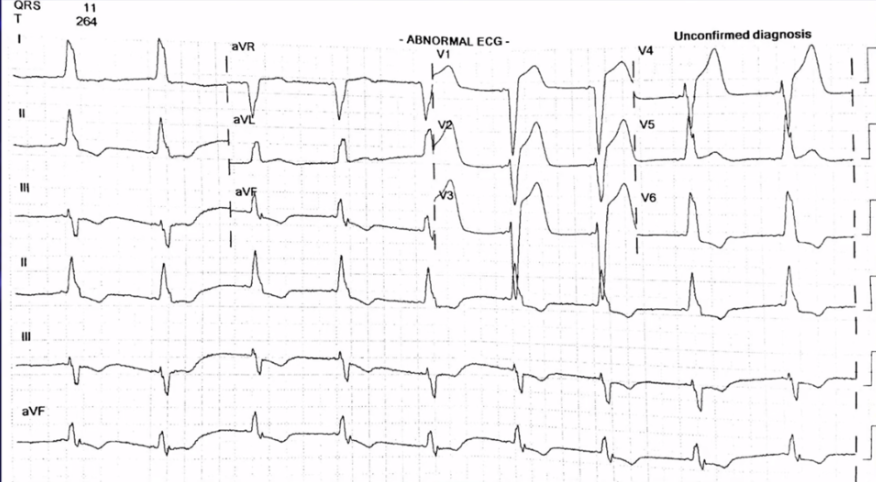

There is 1mm concordant ST elevation in aVL (= 5 points)

There is concordant ST depression in V2-5 (= Sgarbossa positive).

There is 1mm concordant ST elevation in II, III, aVF (= 5 points)

There is 1mm concordant ST elevation in aVL, V4-6 (= 5 points)

There is 1mm concordant ST elevation in aVL (= 5 points)

There is concordant ST depression in V1-3 (= Sgarbossa positive).

There is 1mm concordant ST elevation in aVL, V5-V6 (= 5 points)

There is 1mm concordant ST elevation in I, aVL, V5 (= 5 points)

There is concordant ST depression in V1-3 (= Sgarbossa positive).

There is concordant ST depression in V3 (= Sgarbossa positive).

There is concordant ST depression in V3 (= Sgarbossa positive).

There is 1mm concordant ST elevation in I, aVL (= 5 points)

There is concordant ST depression in V3 (= Sgarbossa positive).

≥ 25% of the depth of the preceding S-wave : Revised Sgarbossa criteria

≥ 25% of the depth of the preceding S-wave : : Revised Sgarbossa criteria